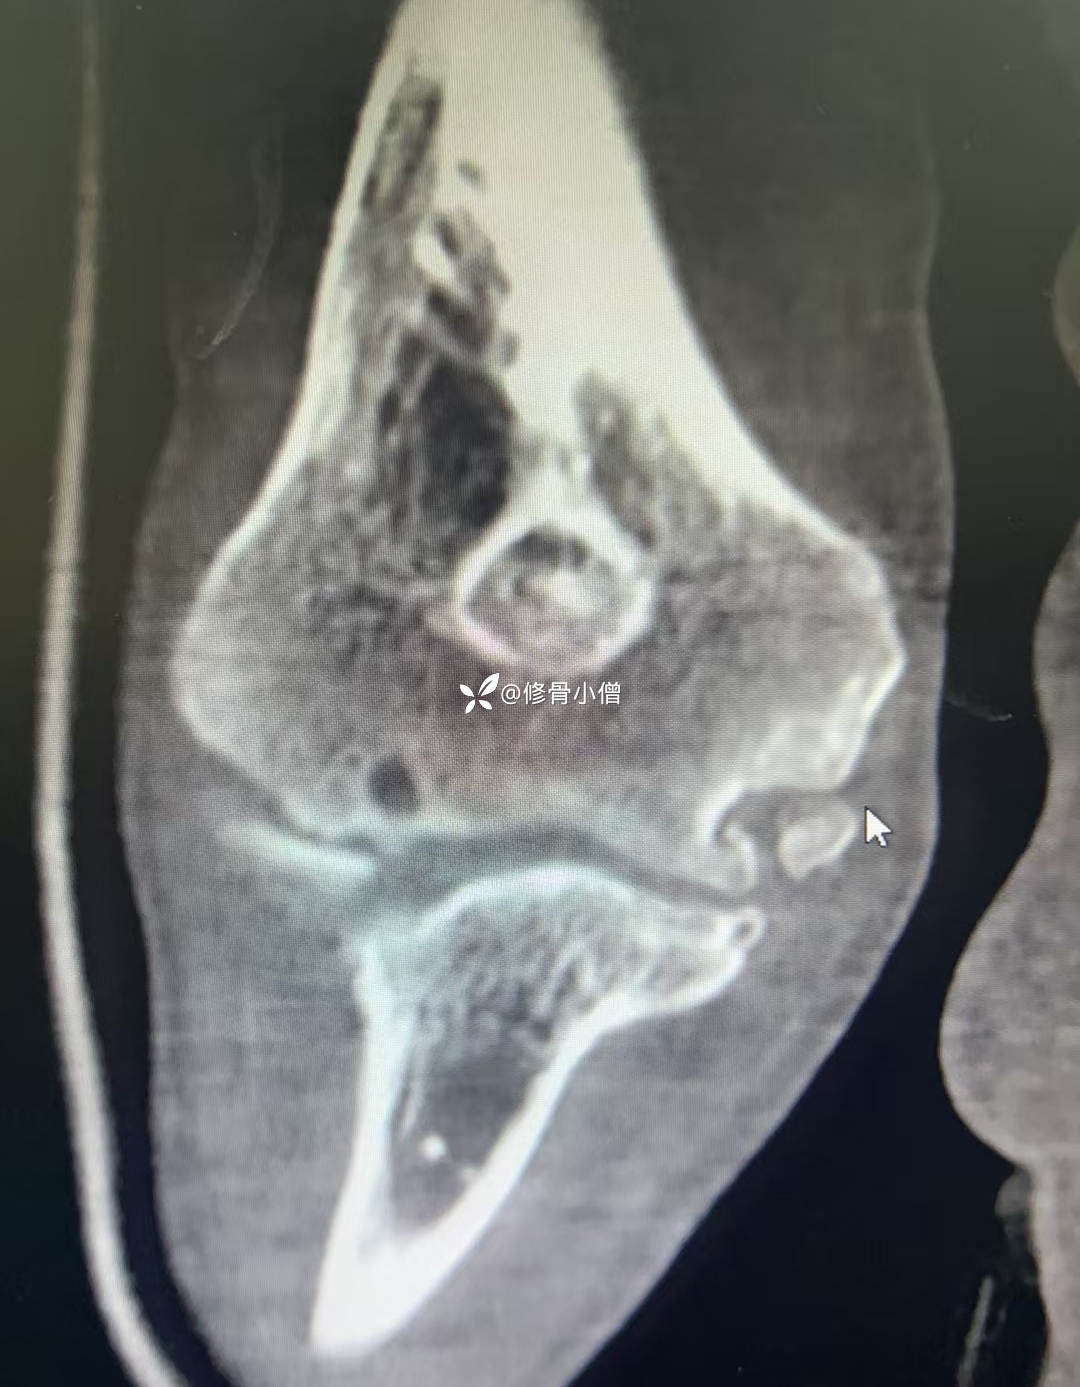

【现病史及既往史】:农民伯伯,留守老年人,该患者于1年前无明显诱因出现右手环指及小指麻木,未予重视,未到任何医院诊治,且环小指麻木渐进性加重,伴环小指爪形畸形,手部肌肉萎缩,其女儿务工返乡后携患者来我院系统诊治。近期一般情况可,体重无增减。既往右肘关节外伤病史10余年。

【检查】:右肘关节外翻畸形,扪及骨性凸起,肘关节屈伸受限,Tinel征:在肘部尺管上、下各 2m 处轻轻叩击尺神经,出现疼痛放射到环指、小指。Froment征:用拇、示指夹纸时,拇指掌指关节过伸,指间关节屈曲。夹纸试验阳性。

【临床诊断】:1.右侧肘管综合症;2.右肘关节外翻畸形;3.右肘关节退行性骨性关节炎。